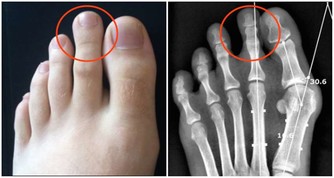

*****10、抽煙*****

抽煙的人以為尼古丁只會進入肺,殊不知,煙霧也會隨著消化道進入胃,直接刺激胃黏膜。引起黏膜下血管收縮、痙攣,胃黏膜缺血、缺氧,長此以往形成胃潰瘍。